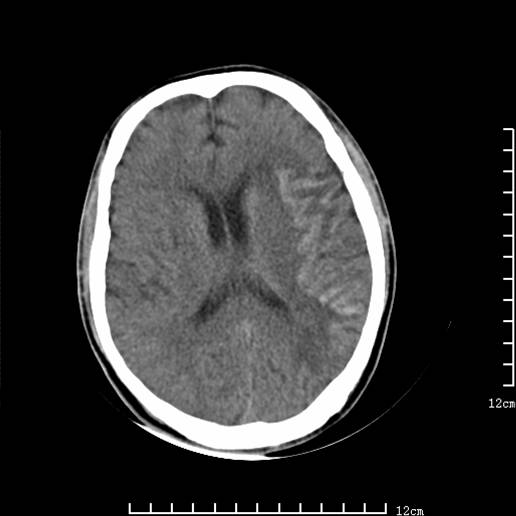

以下图像分别是3月25日凌晨及下午图像、3月27日、4月16日的ct图像。

3月25日凌晨

脑梗塞(左侧大脑中动脉分布区)。

1)左侧额颞顶叶、岛叶及基底节区(相当于左侧大脑中动脉供血区)大面积脑梗塞。2)右侧基底节区腔隙性脑梗塞。

大脑中动脉供血区大面积脑梗塞没有问题。

支持左侧大脑中动脉分布区脑梗塞。